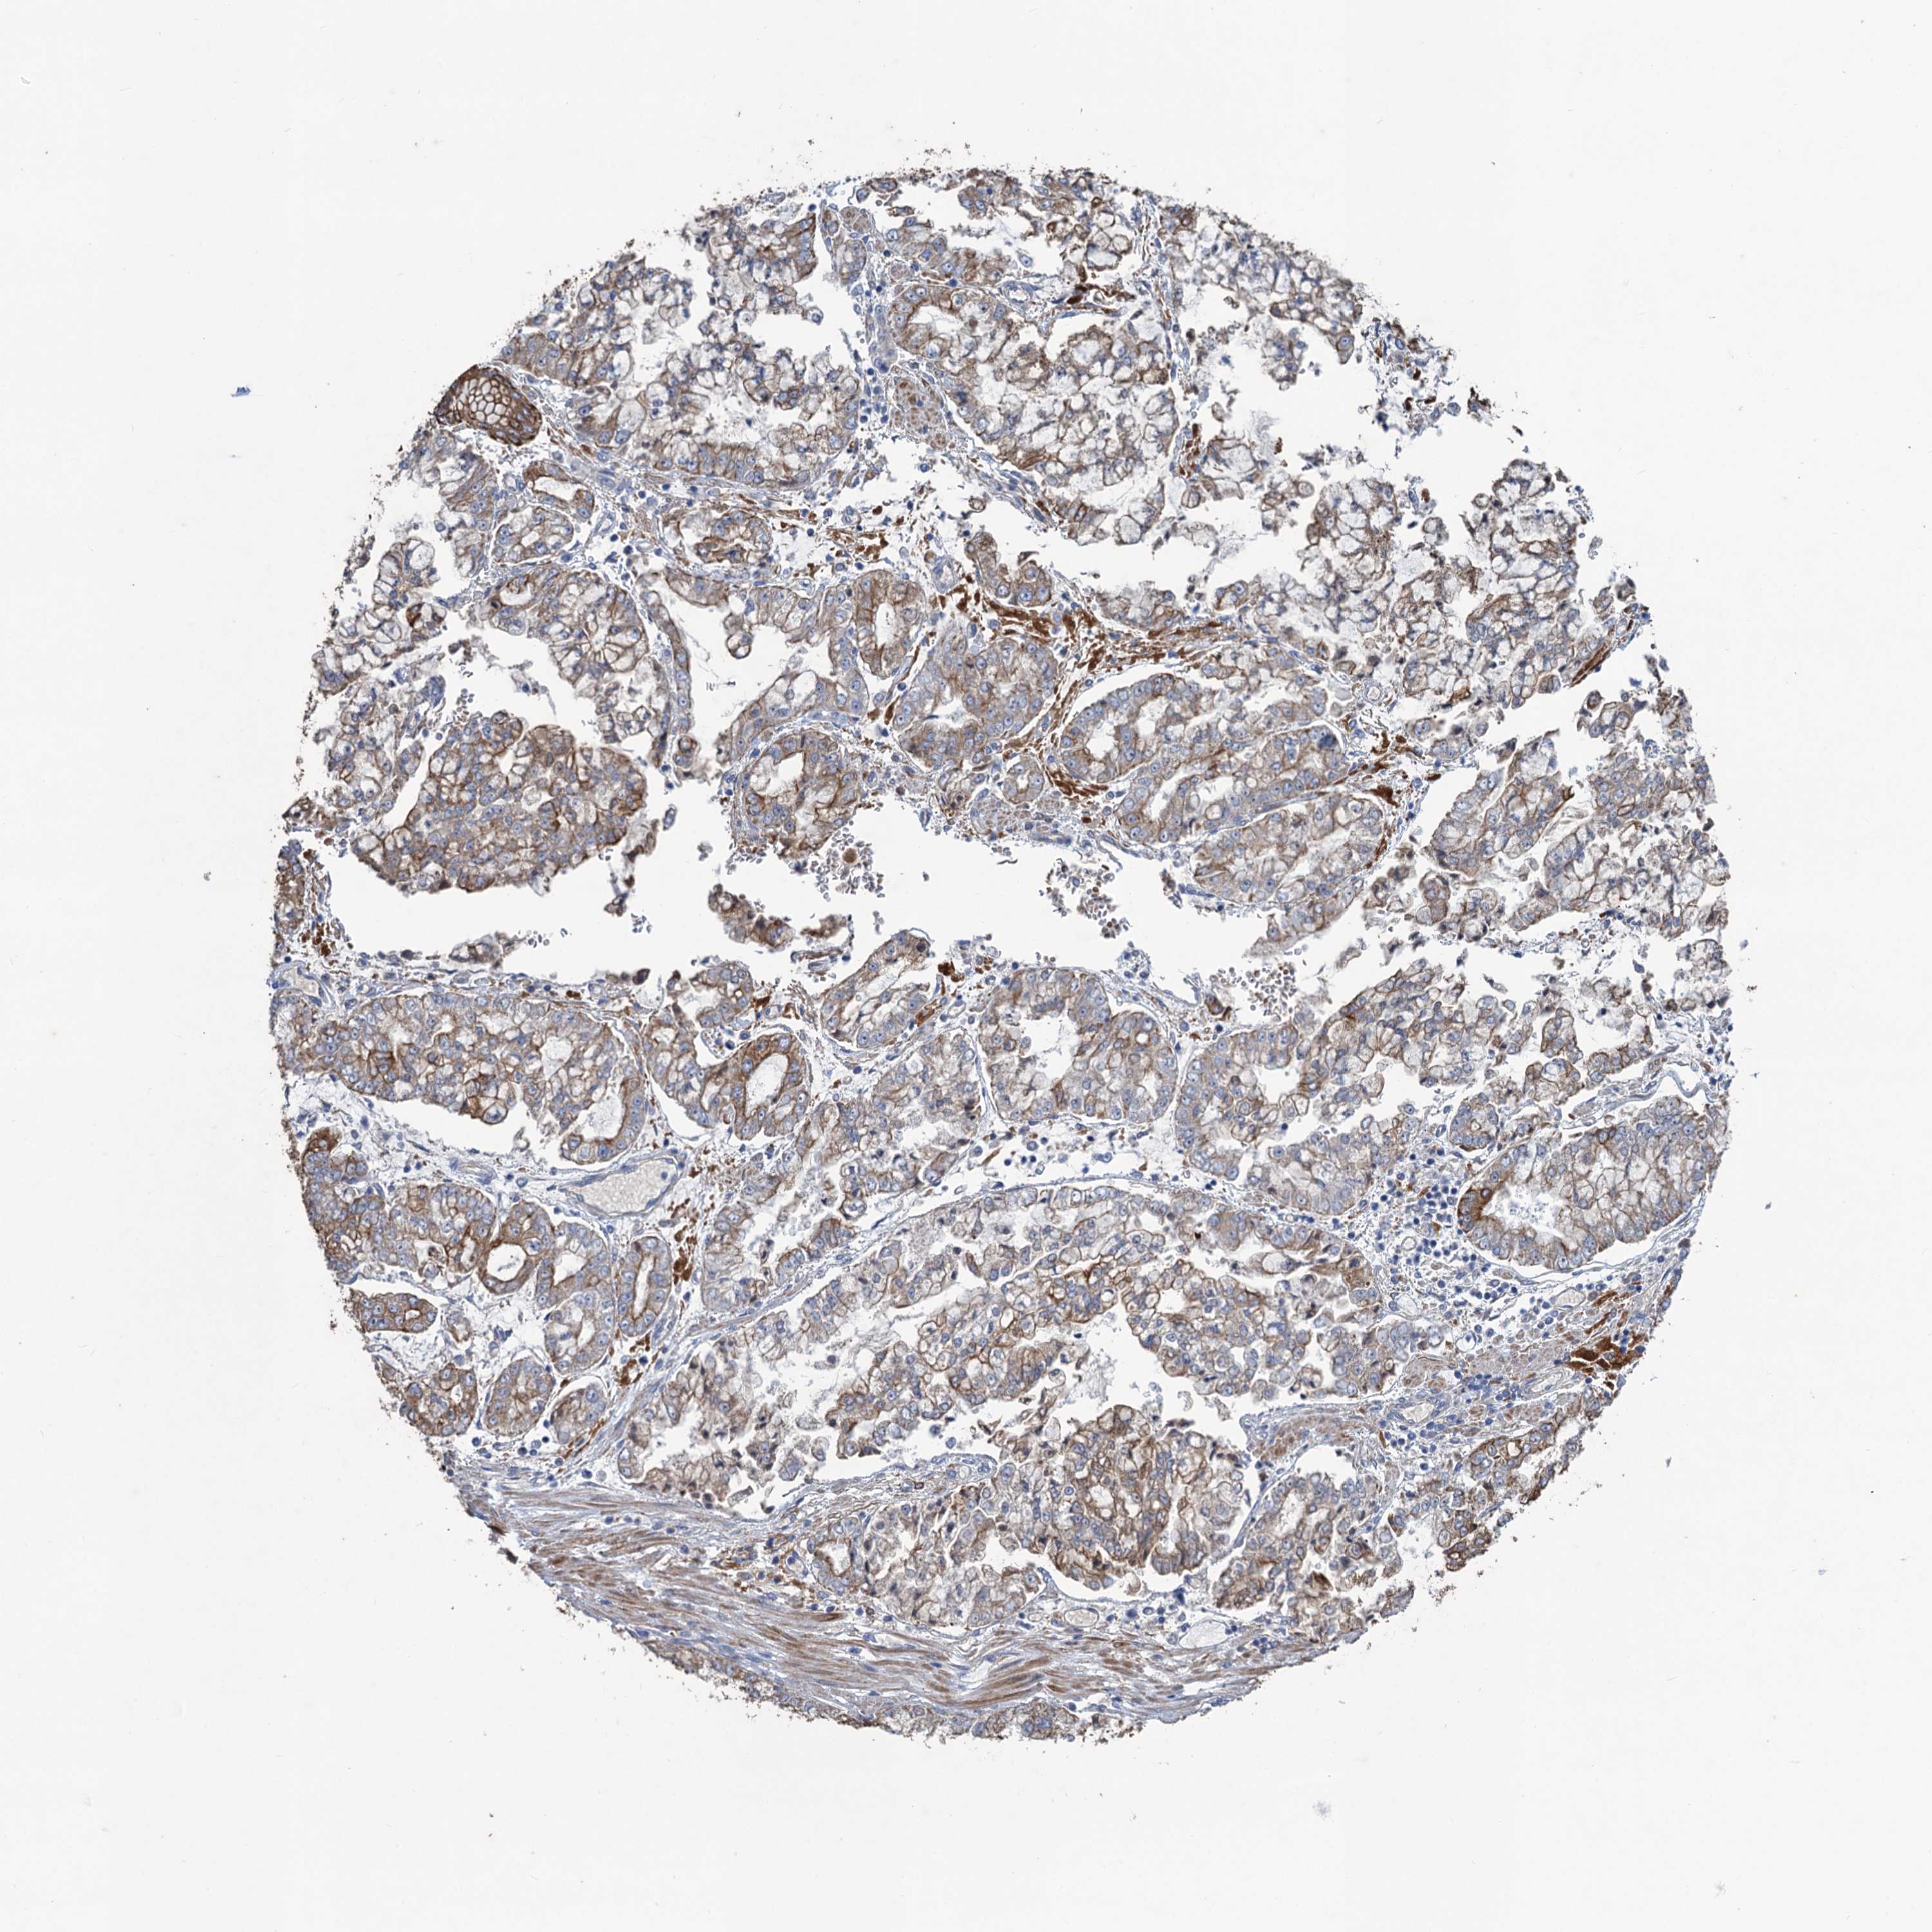

STOMACH CANCER - Protein expressioni

A mouse-over function shows sample information and annotation data. Click on an image to view it in a full screen mode. Samples can be filtered based on level of antibody staining by selecting one or several of the following categories: high, medium, low and not detected. The assay and annotation is described here.

Note that samples used for immunohistochemistry by the Human Protein Atlas do not correspond to samples in the TCGA dataset.

Antibody stainingi

Antibody staining in the annotated cell types in the current human tissue is reported as not detected, low, medium, or high, based on conventional immunohistochemistry profiling in selected tissues. This score is based on the combination of the staining intensity and fraction of stained cells.

Each image is clickable and will lead to virtual microscopy that enables deeper exploration of all samples and also displays staining intensity scores, fraction scores and subcellular localization as well as patient and tissue information for each sample.

Antibody HPA040574

Antibody HPA047804

Staining

High

Medium

Low

Not detected

Intensity

Strong

Moderate

Weak

Negative

Quantity

>75%

75%-25%

<25%

None

Location

Nuclear

Cytoplasmic/membranous

Cytoplasmic/membranous,nuclear

Adenocarcinoma, NOS

Adenocarcinoma, High grade